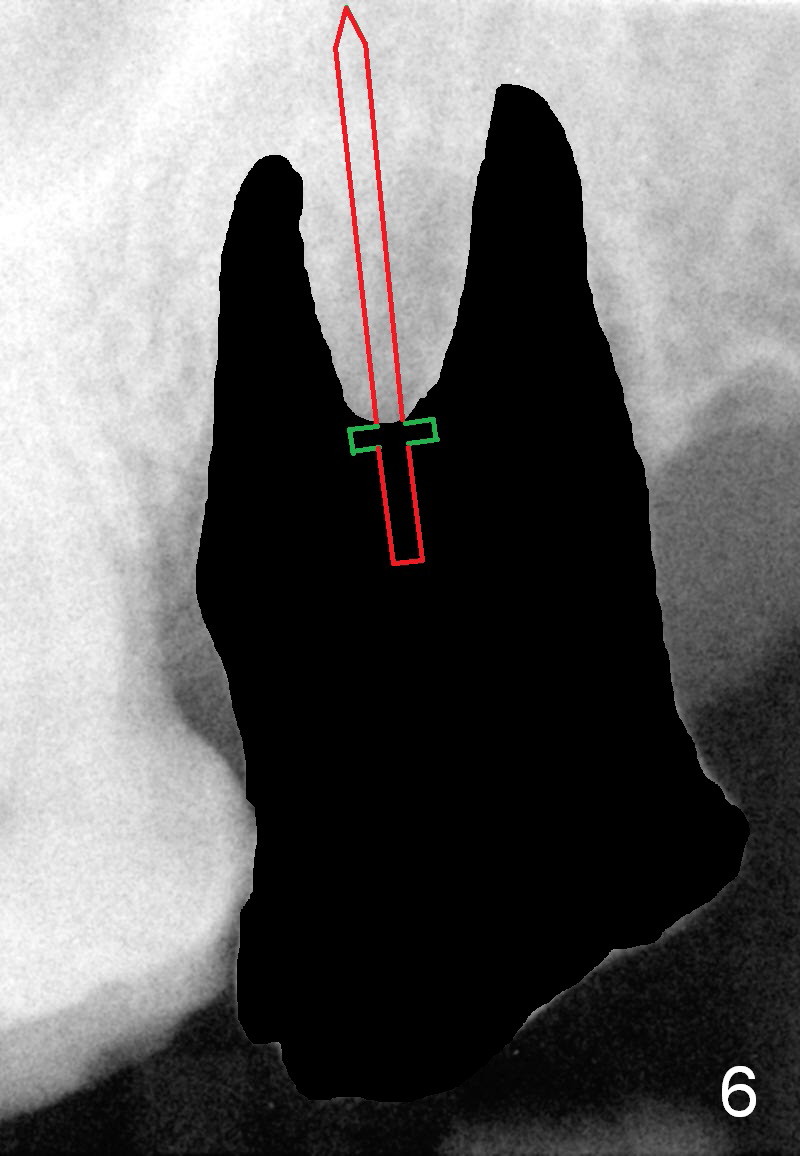

A 53-year-old man (ZB) has history of chronic periodontitis and bruxism. The tooth #18 has been extracted for a few years, while the tooth #15 is going to (Fig.1). Bone height for #15 immediate implant is not a problem (Fig.2-4; green line in Fig.2: sinus floor). After extraction (Fig.5 )socket to be treated with Clindamycin), use starter drill and a 2 mm pilot drill with stopper at 10 mm (Fig.6) on the crest of the septum (Fig.5 S). PA is taken with a parallel pin. Adjust the length accordingly. Subsequent osteotomy will be carried out with drills with stopper at 50 RPM. In brief, the implant does not need to be large. It should be placed as deep as possible (1-2 mm subcrestal mesially and/or distally), since the vertical height in the posterior region is limited. The margin of a cemented abutment is to be slightly subgingival. Use an immediate provisional to close socket gap, while to keep abutment margin from the gingiva. Use Collagen dressing before and after bone graft.